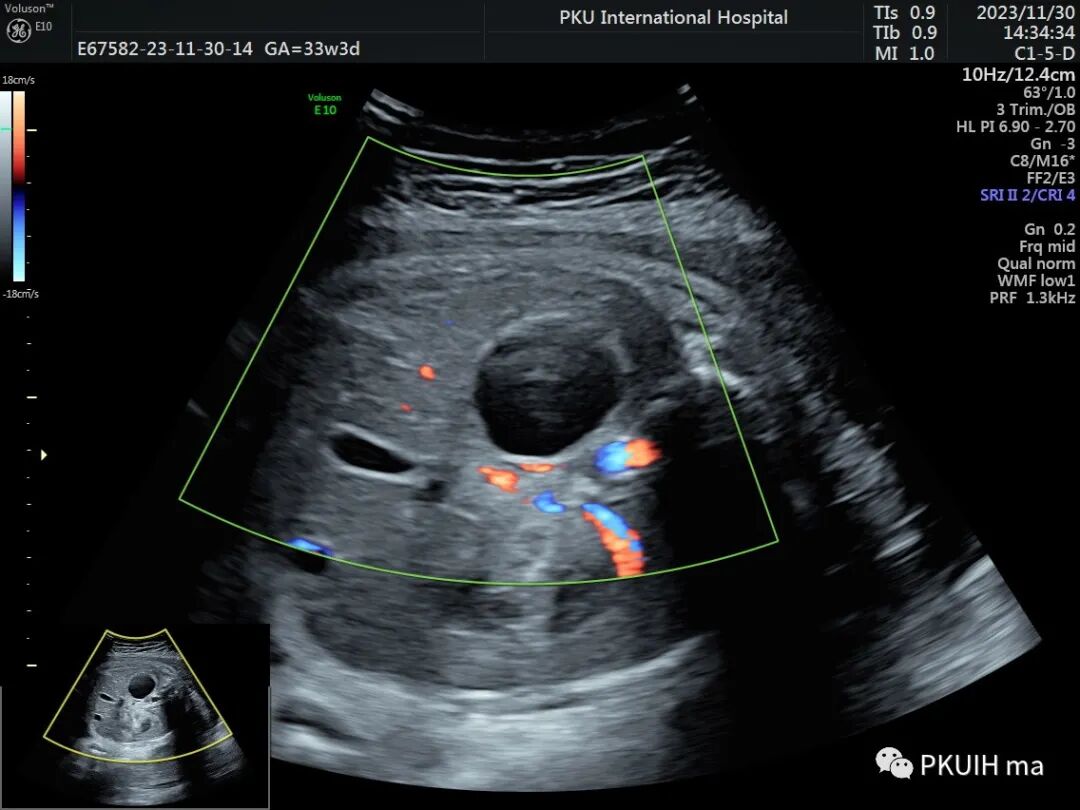

孕妇在之前超声检查中均未见异常,在28周常规超声筛查中发现右侧肾上腺区见一囊肿回声,大小约1.3x1.0cm。随访观察中发现囊肿逐渐增大,胎儿其他各项指标未见明显异常。目前仍在定期随访中

正常情况下,产前超声能够区分腹腔肿块和肾上腺区肿块。肾上腺区肿块的主要鉴别诊断是先天性成神经细胞瘤、隔离肺、肾上腺出血、中胚层性肾瘤和尿道肠道的重复畸形。排除的最重要的病变是成神经细胞瘤。成神经细胞瘤超声图像呈均匀实性回声,部分可呈囊实混合回声,内可见钙化,CDFI肿块内见血流信号,极少部分成神经细胞瘤可呈囊性回声。肾上腺囊性占位需要定期随访,生后没有标准的治疗方案,如果是单纯囊肿<3cm患儿没有症状只需要定期超声。如果出现内分泌失调,生长迅速等需要手术治疗。